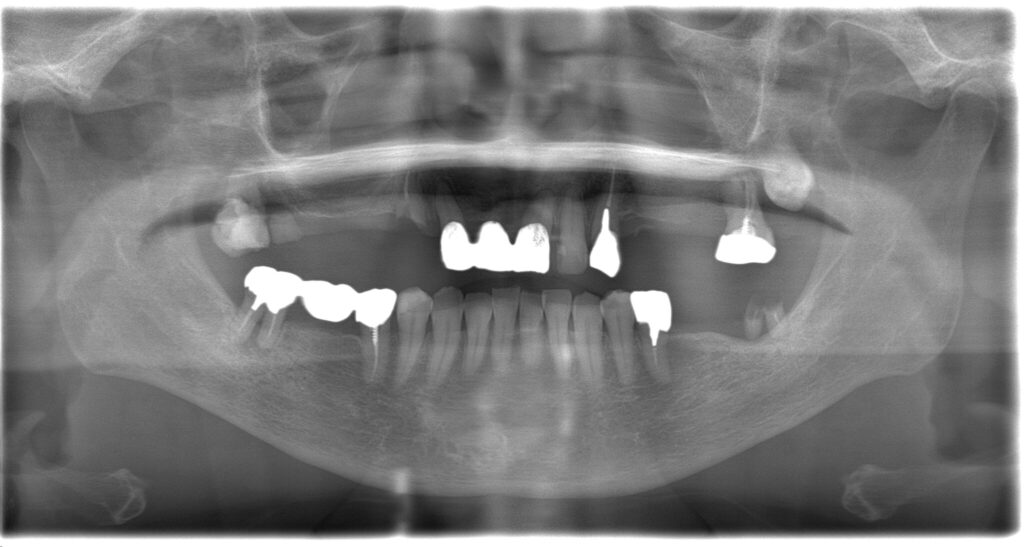

| 診断名・ 主な症状 |

臼歯部欠損 |

| 治療内容 | インプラント埋入(右上4・6,左上4・6,右下6,左下6) ジルコニアBr(右上3―左上3) ジルコニア(右下5,左下5) |